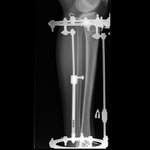

Дата операции 27.09.2016г

Дата снятия аппаратов 15.12.2016г.

Срок лечения 73 дня.